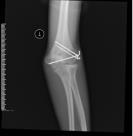

儿童陈旧性孟氏骨折

术前前臂侧位片